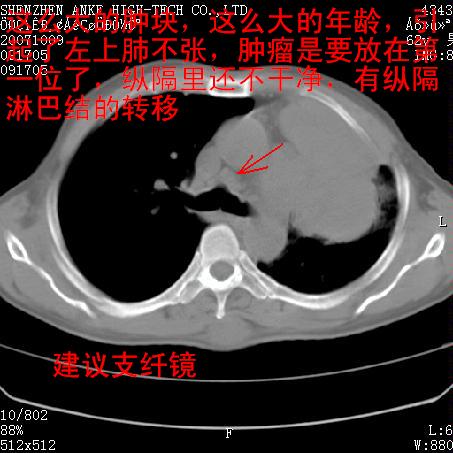

标题: CT9995:男,62岁,会诊,胸部平扫 [打印本页]

患者:男,62岁,咳嗽、胸痛、咯血约2月

左侧中央型肺癌伴上叶肺不张\\阻塞性肺炎.

左侧中央型肺癌伴上叶肺不张、阻塞性肺炎、纵隔淋巴结转移。支持!

左侧中央型肺癌伴上叶肺不张及阻塞性肺炎,纵隔内淋巴结转移